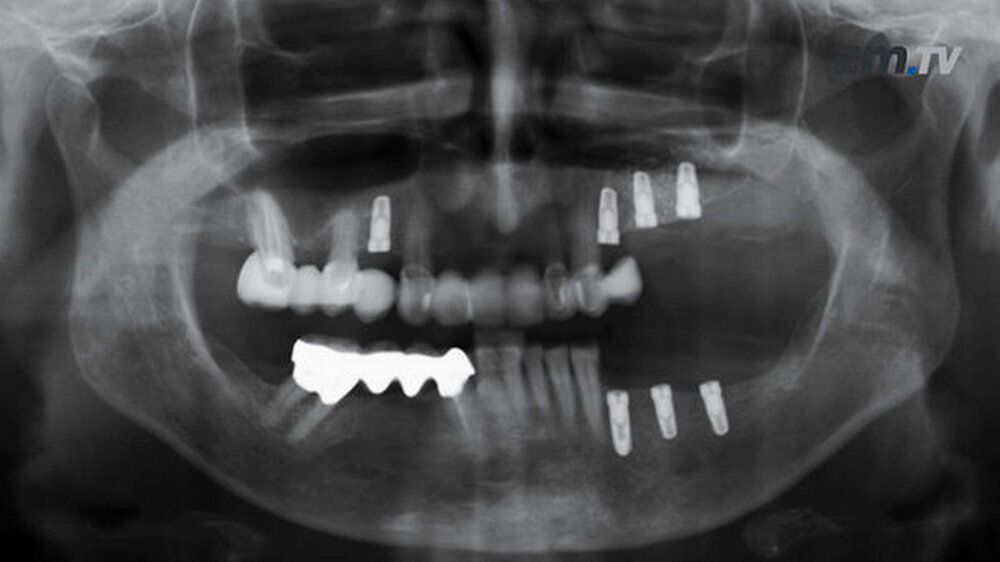

Der Filmpreis 2016 der Arbeitsgemeinschaft für Keramik in der Zahnheilkunde (AG Keramik) geht an Dr. Taskin Tuna, RWTH Universitätsklinikum Aachen, Abteilung Zahnärztliche Prothetik und Biomaterialien. Der dreiminütige Kurzfilm zeigt am Fallbeispiel die Verblendung einer mehrgliedrigen VMK-Brücke im Molarenbereich zwecks Ebenenkorrektur mit einem vollkeramischen Table Top. Der Preis wird auf dem 16. Keramiksymposium am 26. November 2016 in Hamburg übergeben.